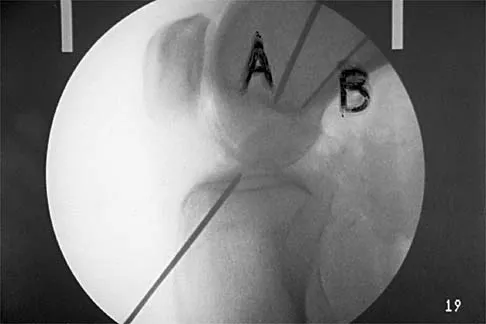

Figure 16 shows the lateral radiograph of a patient who is scheduled to undergo an anterior cruciate ligament (ACL) reconstruction. If the graft is tensioned at 20 degrees of flexion and the femoral tunnel is created by passing a reamer over the guide wire marked "A," the resulting ligament reconstruction will excessively